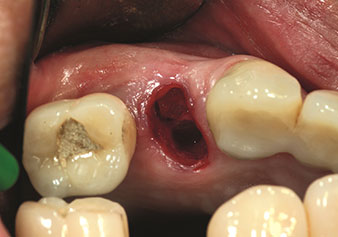

Eine oft unterschätzte Anwendung ist die schonende Extraktion von Zahnwurzeln oder auch von Wurzelfragmenten im Rahmen des Alveolenmanagements. Mit den feinen Periotomen, die aktuell in zwei Ausführungen (EX1 und EX2 von W&H) zur Verfügung stehen, lassen sich auch speziell endodontologisch vorbehandelte Zähne oder ankylosierte Wurzeln mühelos entfernen. Das Ergebnis sind Extraktionsalveolen, deren Hart- und Weichgewebe völlig intakt sind, da in der Regel auf ein Aufklappen verzichtet werden kann.

Dies stellt anschließend eine optimale Basis für eine spätere oder Sofortversorgung mit Implantaten dar (Abbildung eins und zwei mit freundlicher Genehmigung von Dr. Torsten Conrad, Bingen a. Rhein).

Foto: © Dr Torsten Conrad (Bingen a. Rhein)